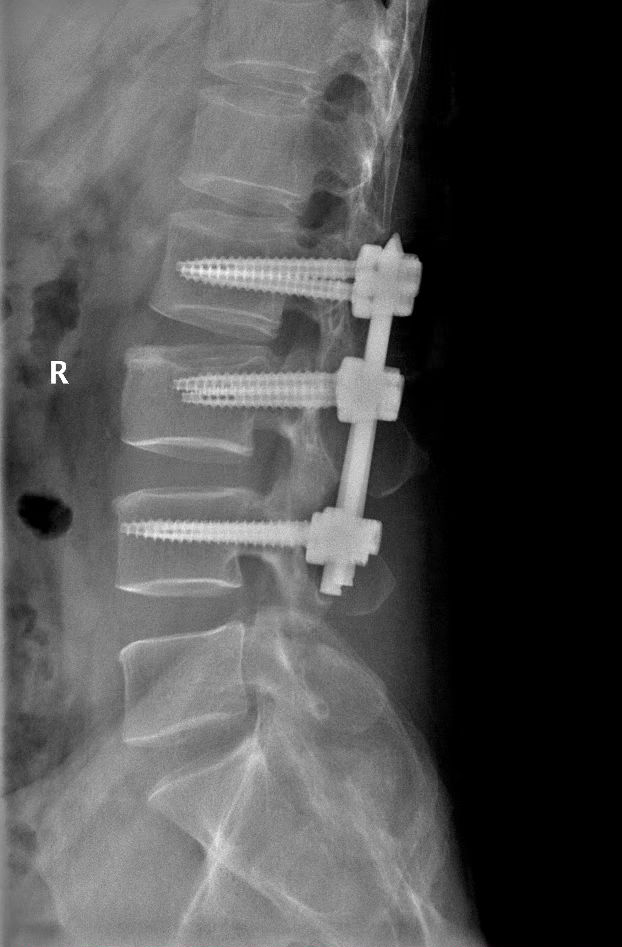

在 C 臂机的定位下,李清主任先是在患者背部开 6 个约 1.5 厘米长的小切口,然后植入 6 枚弓根钉和连接棒,对受伤的腰椎进行复位并固定。手术时长 50 分钟,术中几乎没有出血。